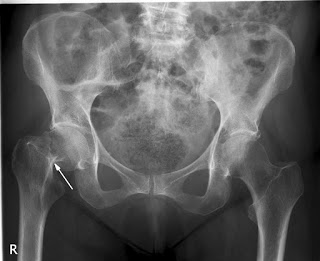

Cirugía de cadera ultrarrápida

En pacientes con fractura de cadera, la cirugía en las primeras seis horas del diagnóstico no obtuvo mejores resultados que la realizada a las 24 hs del mismo. The Lancet, 29 de febrero de 2020.